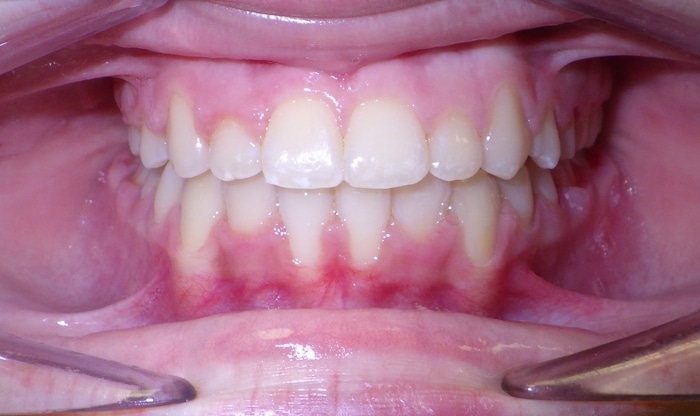

EMILY’S SMILE JOURNEY

Emily began with us as a Phase I patient and we just recently debanded her from Phase II. These progression photos show you that starting early allows us to not just straighten the teeth, but also change the patient’s jaw shape. Emily was a dedicated patient and did great with treatment. Her results speak volumes! We were able to correct her severe underbite and Class III skeletal imbalance without needing jaw surgery.